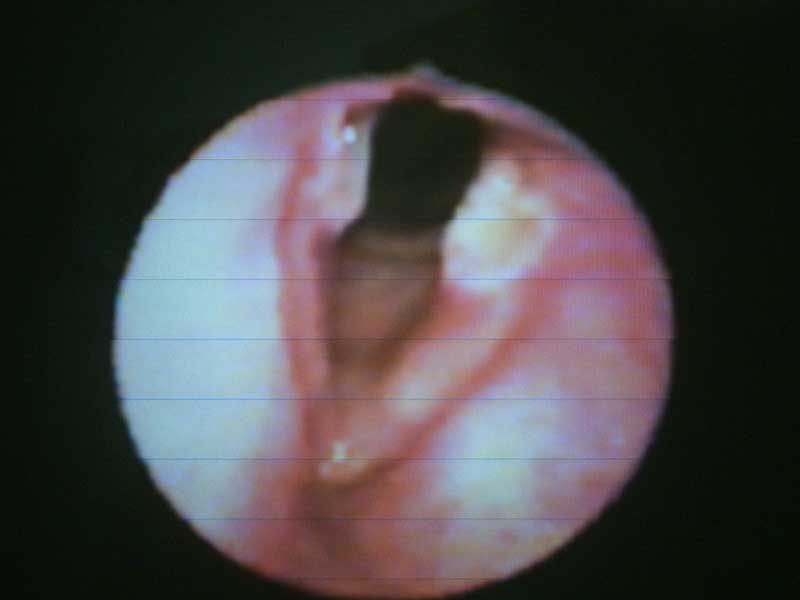

Úlceras de contacto en un paciente 5 días después de habérsele retirado el tubo oro-traqueal y haber permanecido un tiempo en una unidad de cuidados intensivos. Este tipo de pacientes presentan comúnmente este tipo de lesiones debido a la irritación del ácido gástrico en este nivel.